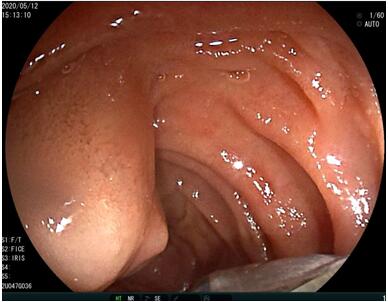

69歲王姓患者,因“發(fā)現(xiàn)無痛性黃疸1月”入院,根據(jù)患者病史,患者診斷傾向于壺腹部腫瘤所致梗阻性黃疸。予以完善腹部CT及上腹部MRI加MRCP均顯示肝內(nèi)外膽管擴(kuò)張,未發(fā)現(xiàn)明顯膽管,胰腺及十二指腸乳頭部腫瘤,且患者CA199正常。以前醫(yī)院未引進(jìn)超聲內(nèi)鏡,這類患者到此就遇到診斷瓶頸。此患者經(jīng)過消化內(nèi)科張丹霞副主任醫(yī)師完善超聲內(nèi)鏡檢查后,可以清楚顯示膽總管下段壁內(nèi)軟組織占位。患者通過超聲內(nèi)鏡檢查診斷明確,轉(zhuǎn)至肝膽外科行手術(shù)治療。

超聲胃鏡圖片